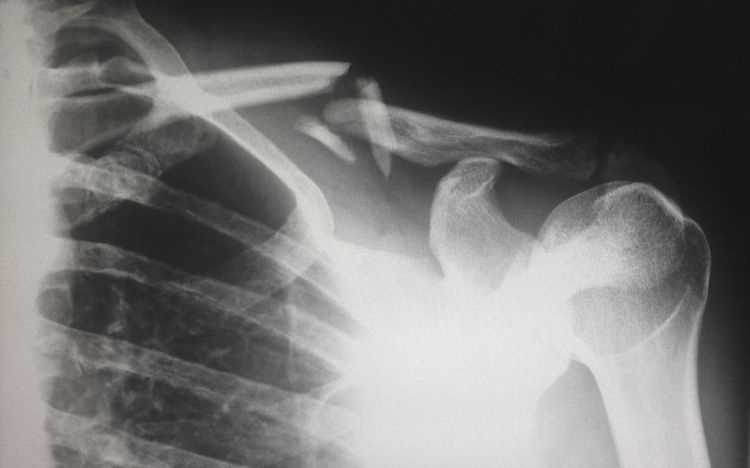

Рентген открыл глаза на многие вещи

«Когда рентгеновские технологии впервые стали широко доступны педиатрам, они заметили поразительно большое количество сломанных костей на снимках. Сбитые с толку врачи предположили, что они наблюдают ранее неизвестное заболевание костей у детей. Оказывается, врачи просто не имели понятия о том, насколько в семьях было распространено жестокое обращение с детьми».